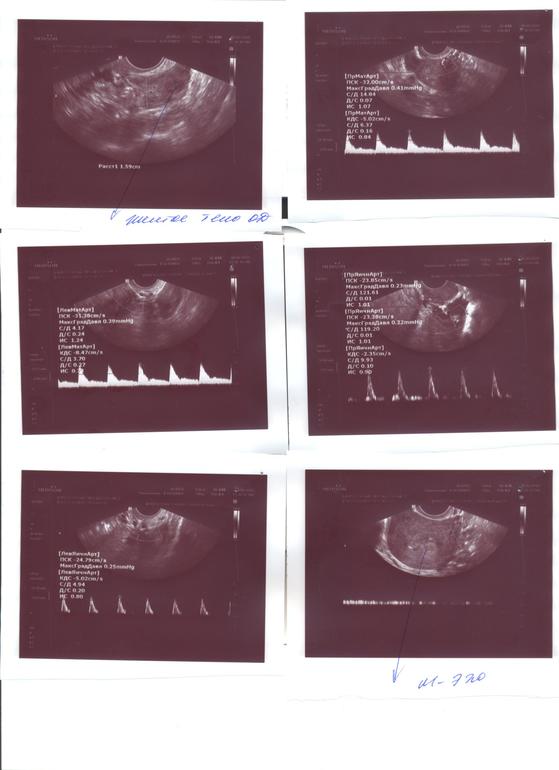

Допплер сосудов матки. При таком заключении нужна физиотерапия?

Мне перезвонила новый врач, она пересмотрела мою карту и анализы, за что ей ОГРОМНЕЙШЕЕ СПАСИБО, уточнила, что я сейчас принимаю (Омега 3, ДГЭА, тардиферон, ангиовит, дексаметазон,фолацин, тромбо Асс) отменила тромбо и назначила актовегин по 2 таб. 3 р. И сказала,что допплер не очень нравится. На осмотре (мне назначила на 23-25 дмц) будет смотреть и возможно направит на физиотерапию...

Но ! Мне назначали допплер делать только на 17 дмц (хотя в Пластике перепутали), а не с 23 по 25 дмц... Когда все таки смотрят этот допплер???